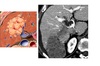

CT enterography features of active Crohn’s disease

**mucosal hyperenhancement **- most sensitive indicator but seen in other bowel diseases most specific sign for chrons - **Prominence of the vasa recta adjacent to the inflamed loop of bowel (comb sign) along with increased mesenteric fat attenuation** wall thickening (thickness >3 mm) CT enterography to depict extra-enteric disease/complications including -obstruction -sinus tract -fistula and abscess formation long-standing/inactive features include -submucosal fat deposition -pseudosacculation -surrounding fibro-fatty proliferation -fibrotic strictures MR enterography and enteroclysis - MR enteroclysis was superior to MR enterography in demonstrating mucosal abnormalities. -MR enteroclysis better bowel distension but not necessarily better diagnostics -MR enterography is more acceptable to the patient than MR enteroclysis